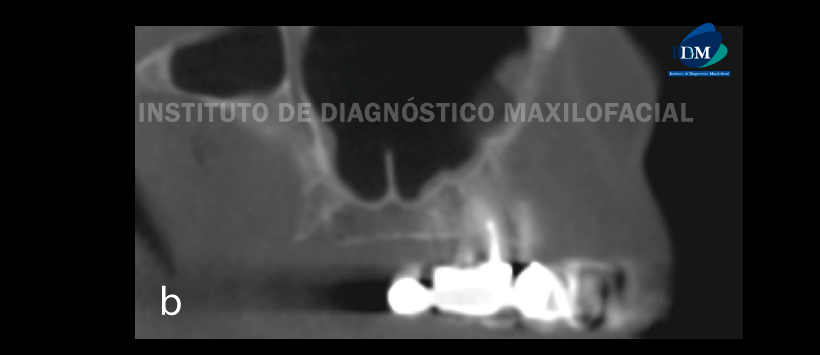

Figura 1: Orientación de los tabiques: (a) tabique sagital que se muestra en un corte coronal del seno maxilar; (b) tabique coronal mostrado en un corte sagital del seno maxilar, (c) tabiques transversales mostrados en un corte sagital del seno maxilar.

Figura 3: Orientación de los tabiques en CBCT: (a) sagital, (b) coronal, (c) transversal.